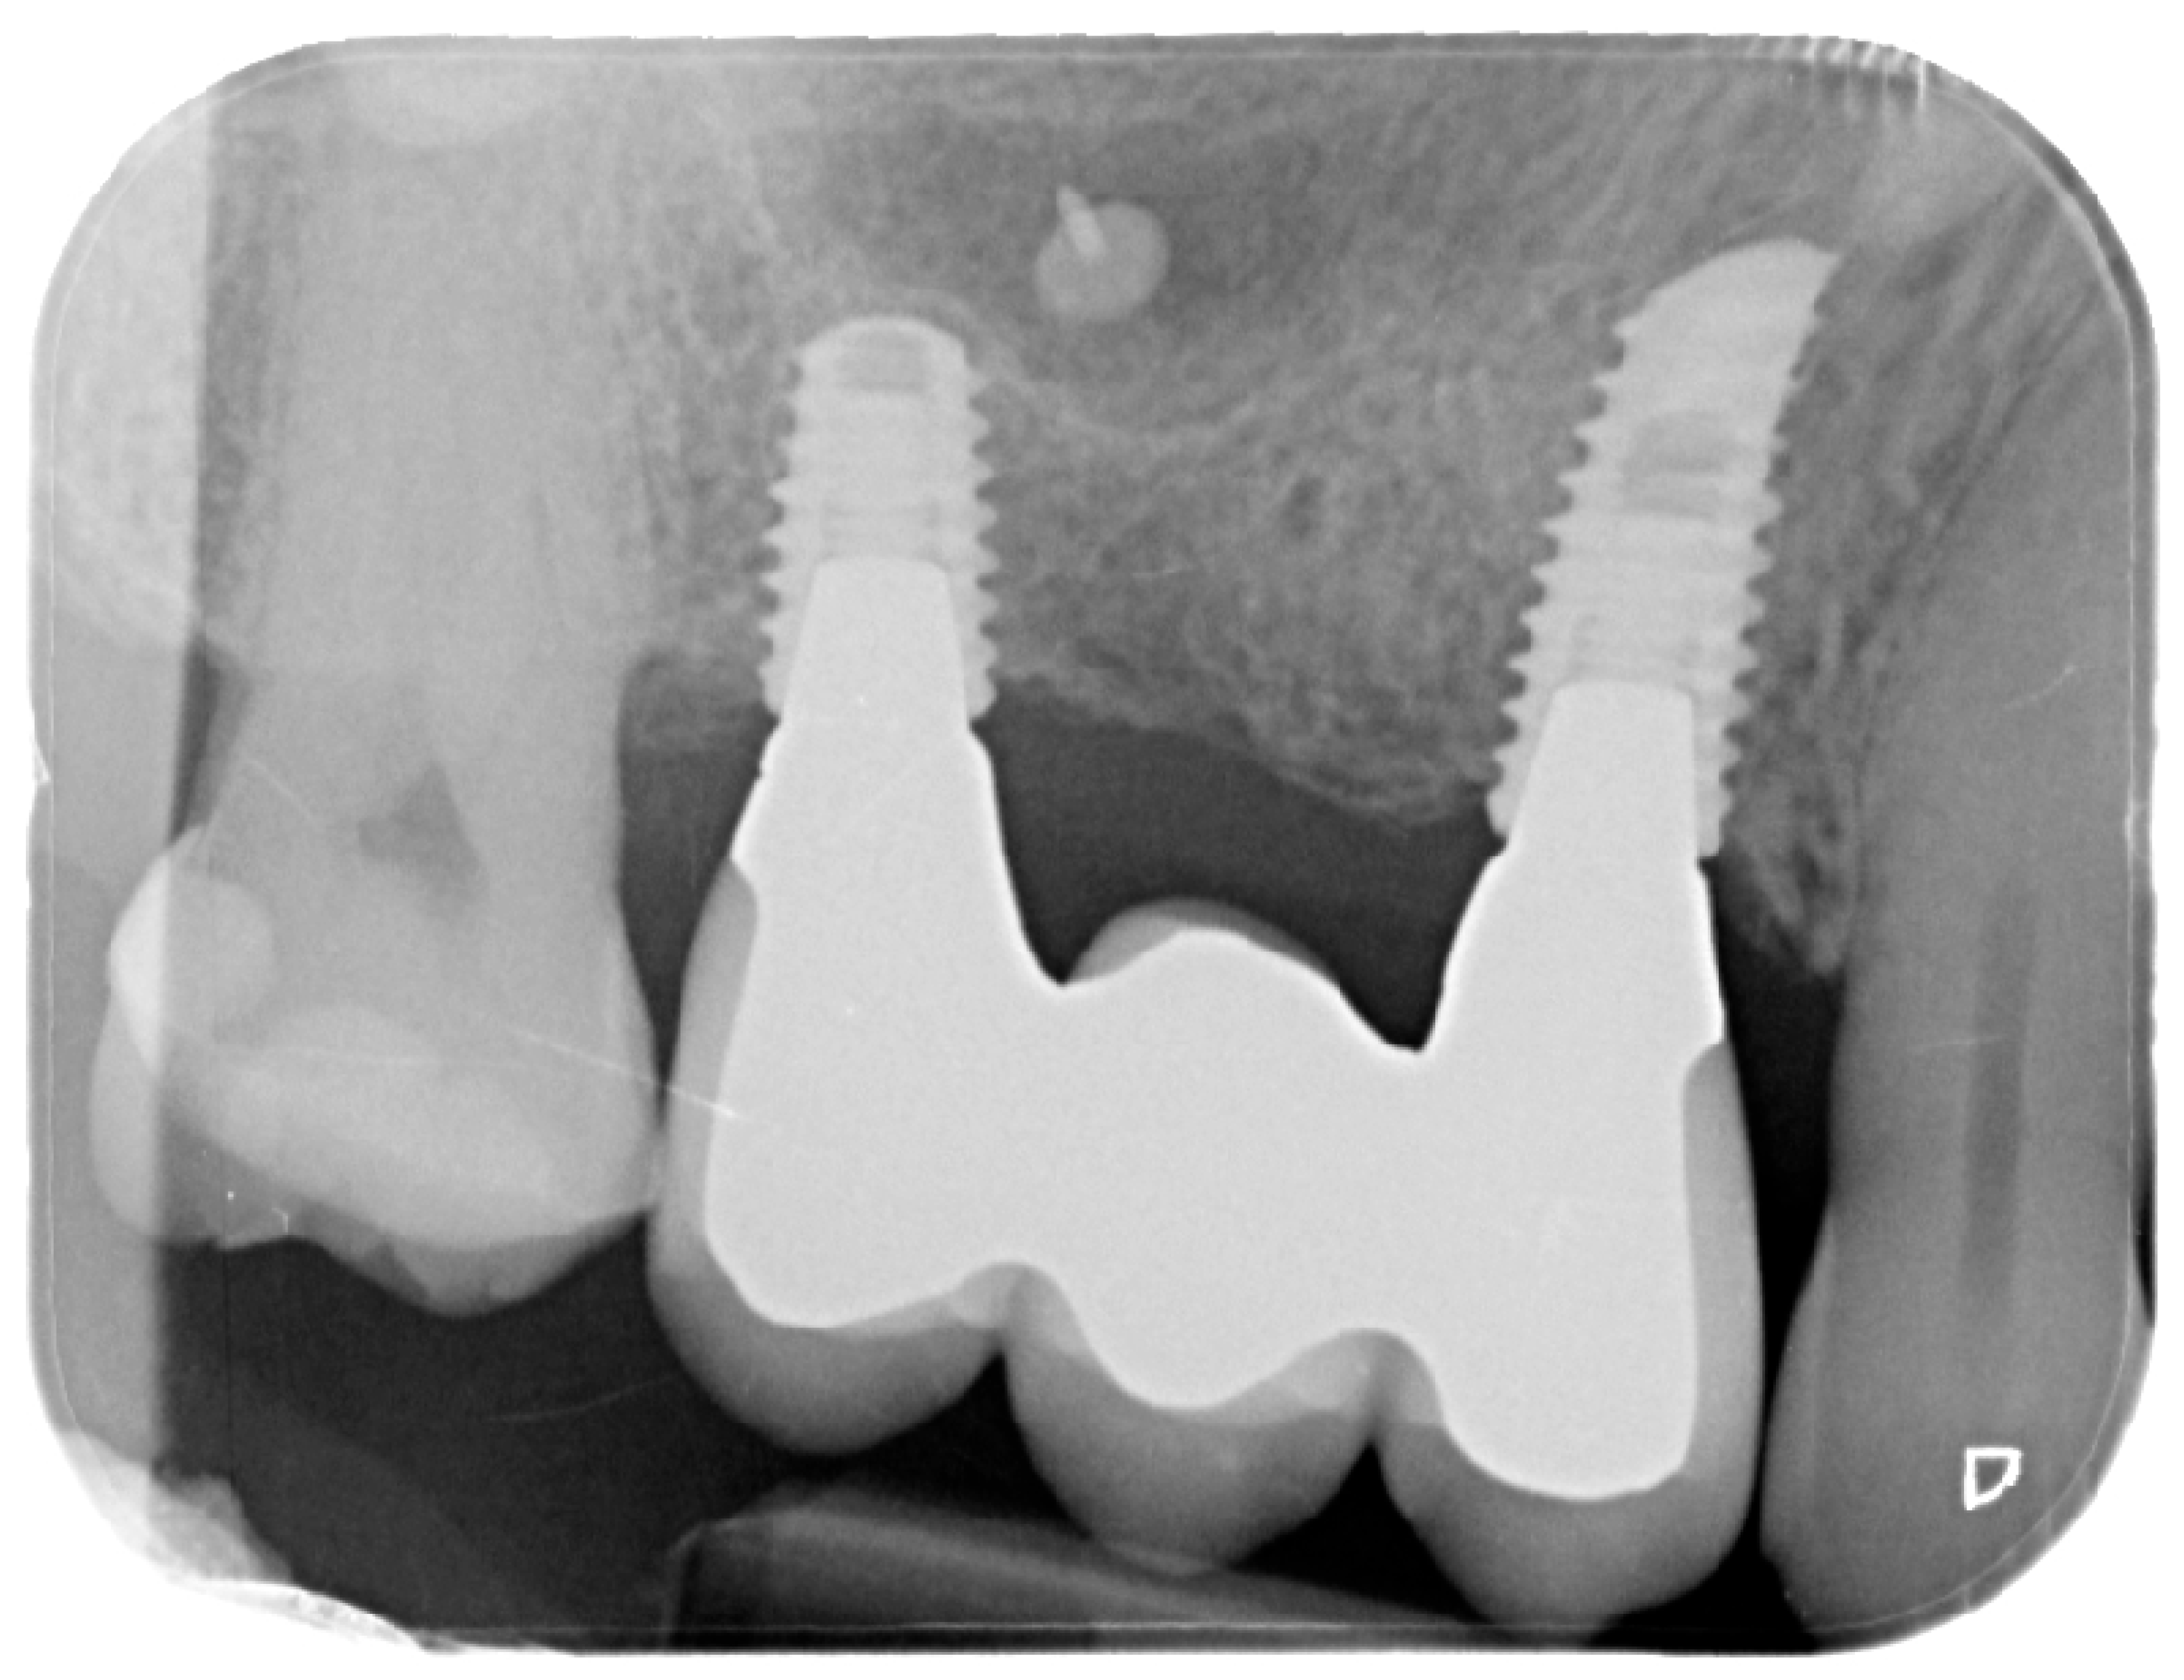

For the evaluation of the mesial and distal MBL, intraoral digital radiographs were taken using the long-cone paralleling technique with the central beam directed to the alveolar crest. Periapical radiographs were taken at the delivery of the prosthesis and after 1 year of prosthetic loading (T2). The mesial and distal MBL, i.e., the distance between the top of the implant shoulder and the first visible bone-to-implant contact, were measured at the mesial and distal aspect with a 10–15× magnification using an image analysis programme (ImageJ v 1.49, NIH, Bethesda, MA, USA). The length of the implant was used as known measure for the calibration and determination of the exact magnification and distortion of the images. All measurements were performed by two examiners to the nearest 0.1 mm. In case of disagreement, the evaluation was re-done and results discussed until an agreement was found.

Figure 8. Postoperative intraoral X-ray.

Figure 12. Intraoral X-ray at delivery of the final prosthesis.